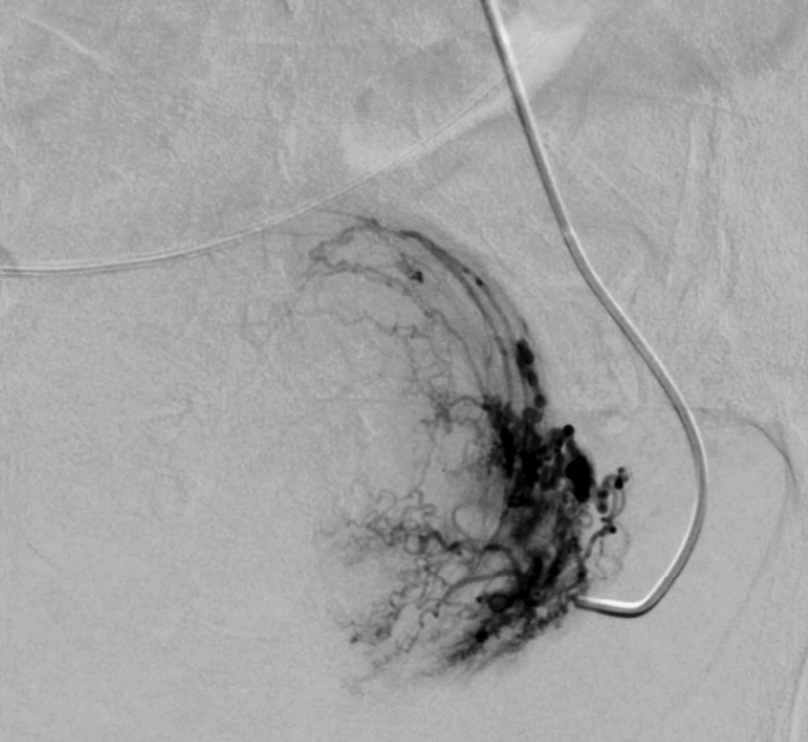

Выполнены пункция и катетеризация правой лучевой артерии в ретроградном направлении. Далее катетером выполнена селективная катетеризация правой и левой маточных артерий. Выявлена миома матки больших размеров с выраженным перифиброидным сплетением. При проведении ангиографии брюшной аорты и таза дополнительных источников кровоснабжения не выявлено. Катетер по проводнику проведен последовательно в горизонтальные сегменты левой и правой маточных артерий, питающих узлы (рис. 2, 3). Проведена эмболизация насыщенными гадотеридолом микросферами до стаза контраста в дистальных сегментах маточных артерий. Рентгеновский контроль эффективности эмболизации – на рис. 4, 5. Катетер и интродьюсер удалены. Наложена давящая асептическая повязка.

Рис. 2. Клинический пример №1. Ангиограмма правой маточной артерии до ЭМА. / Fig. 2. Clinical case 1. Angiogram of the right uterine artery before UAE.

Рис. 3. Клинический пример №1. Ангиограмма левой маточной артерии до ЭМА. / Fig. 3. Clinical case 1. Angiogram of the left uterine artery before UAE.